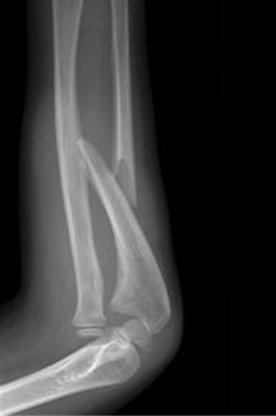

Monteggia fractures

This is a displaced ulna fracture, usually proximal, with a radial head dislocation. To identify a radial head dislocation, check that the capitellum and radial head are aligned on AP and lateral X-rays.

The treatment for Galeazzi and Monteggia fractures usually involves anatomical reduction and fixation of the fractured bone. This leads to spontaneous reduction of the dislocated joint. These fractures should always be referred urgently.